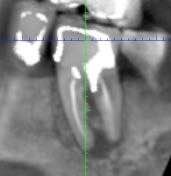

Вот вам реальный клинический случай. Крестальная перфорация в области четырёх миллиметров от вершины альвеолярного отростка, очаговое разрежение костной ткани и уже сформировавшийся пародонтальный карман. Звучит как приговор, и если честно, в данном случае так и есть, потому что такой зуб это уже прямое показание к удалению.

Всё дело в близости к зубо-десневой бороздки. Когда перфорация возникает в этой зоне, воспаление окружающего пародонта запускается практически мгновенно, а следом за ним начинается миграция эпителия зубодесневой бороздки вниз, и буквально за считанные недели формируется полноценный пародонтальный карман. После этого спасать уже нечего.